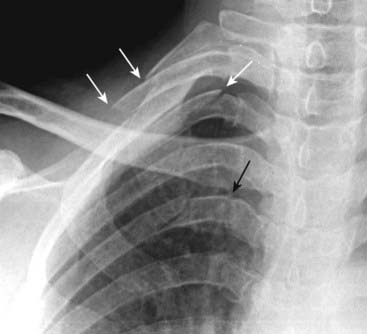

image

Figure 17-3 Pulmonary contusions, chest radiograph and CT.

A, Pulmonary contusions tend to be peripherally placed most frequently at the point of maximum impact (dotted white arrow). Air bronchograms are usually not present because blood fills the bronchi as well as the airspaces. B, A second patient, who was in an unrestrained passenger in an automobile accident, also has a large contusion (solid white arrow) associated with multiple rib fractures (solid black arrows).